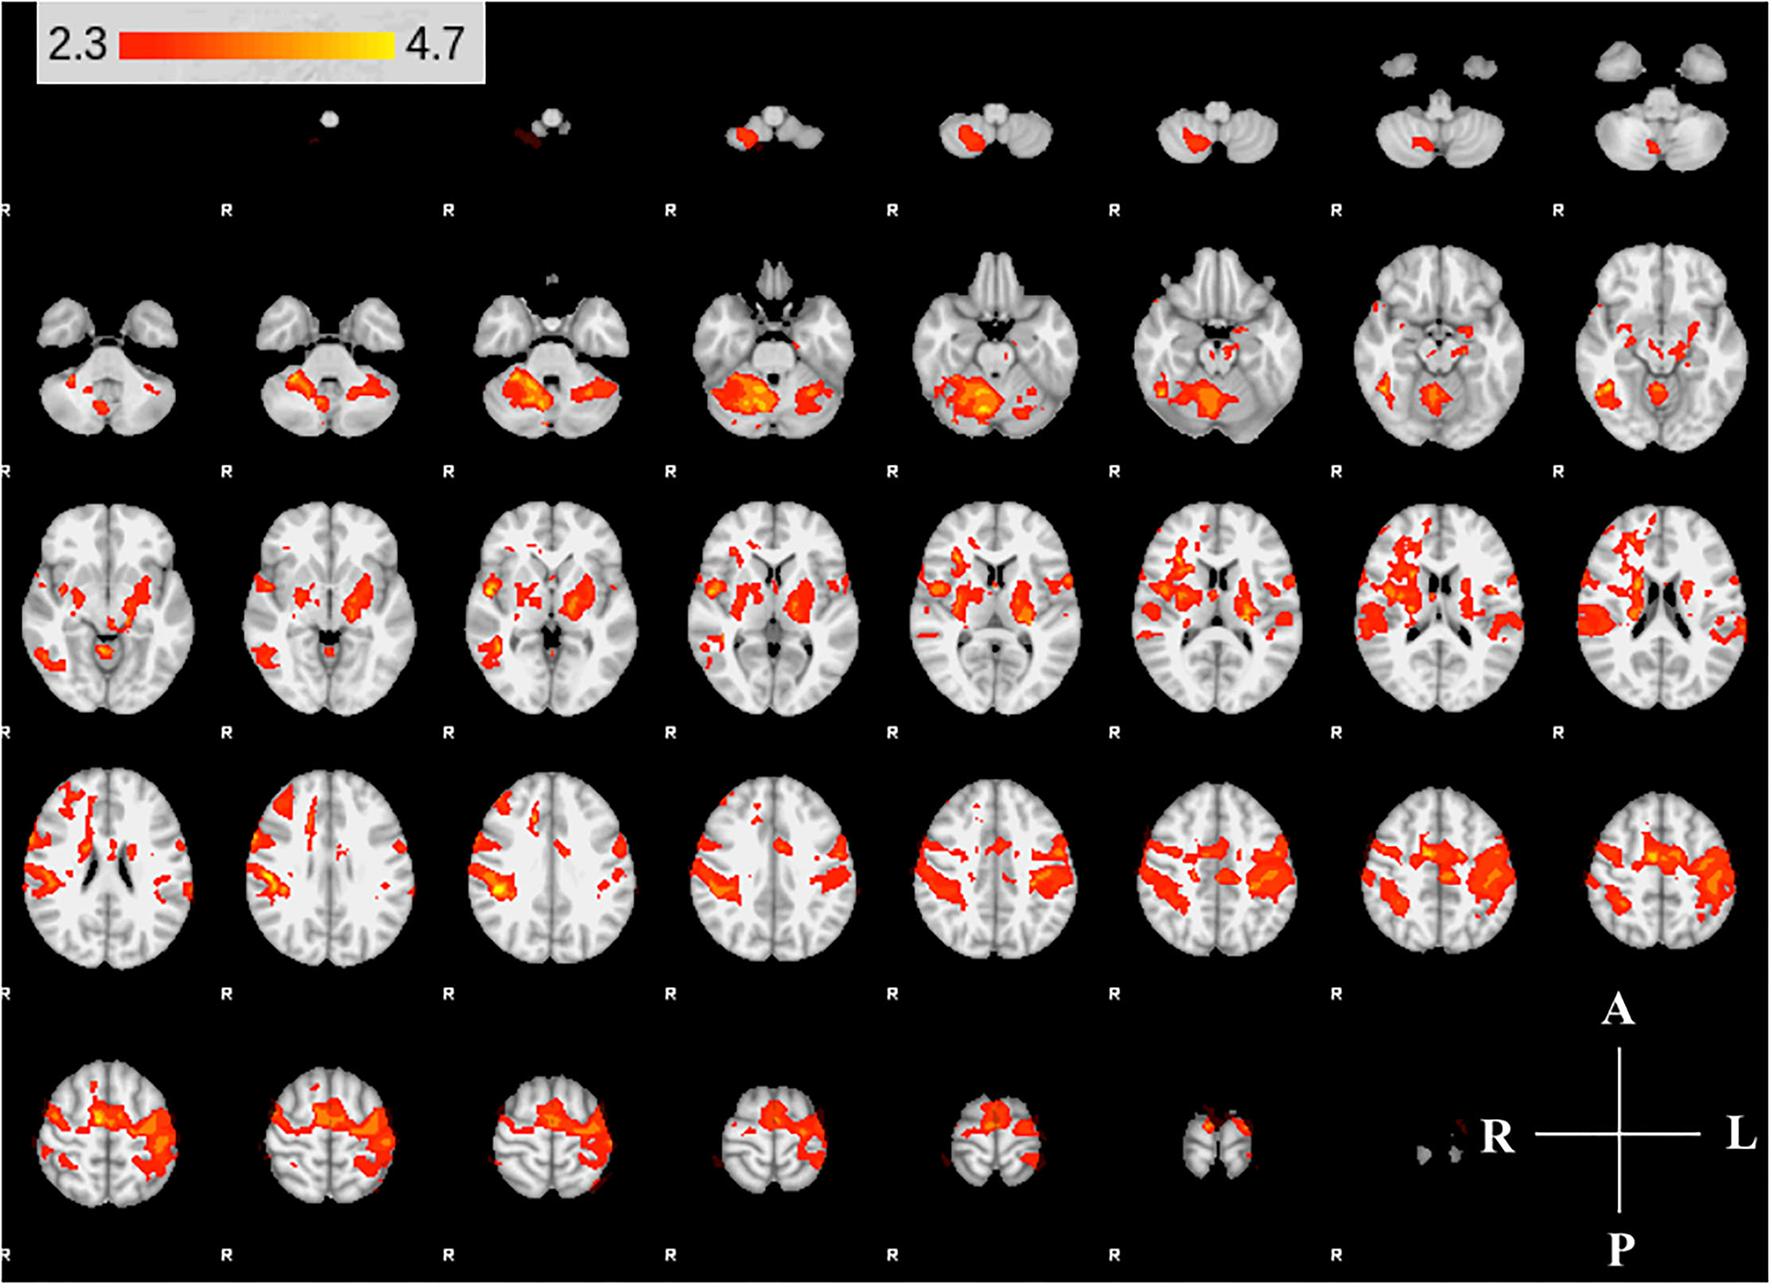

We found expected activity patterns and no significant difference between W0 and W6 sessions for controls. Across sessions, controls consistently and significantly activated bilateral primary motor (M1) and ipsilateral cerebellar areas at W0 and W6 (Figure 4) during right-hand movement. In addition to these regions, the ipsilateral premotor and supplementary motor area, bilateral hand portion of the M1, the thalamus and the putamen showed significant task-related activity. Although control participant's activity maps were similar across sessions, stroke participants showed differences between W0 and W6 (Figure 5). At W6 there was more widespread and bilateral activation in the stroke group compared with W0; whereas activation before injection was restricted to the contralesional hemisphere, activation increased in both hemispheres after injection (Figure 5). Activation maps yielded p-values for each voxel; these maps were threshold with p < 0.05 to assess significance. Significant differences (p < 0.05, df = 8; z > 2.3; paired z-test) between W6 and W0 in the stroke group included: (1) contralesional premotor cortex (PMC-R), (2) contralesional cingulate gyrus (CG-R), (3) contralesional thalamus (Th-R), (4) somatosensory and visual integration areas (Sens-IA), and (5) superior cerebellum (S-CB). These regions of activation are further described in Table 4 and illustrated in Figure 5.

Figure 4

Group activity maps of control participants. The figure shows slices of the MNI template overlaid with z-statistic (Z > 2.3) maps of W0 and W6 average control group activity during non-dominant hand movement. Activity maps indicate volumes in which there was significant (p < 0.05) levels of activity across the group. The right hemisphere of the brain is displayed on the left. Right hemisphere is ipsilateral to the movement arm. No differences were detected between W0 and W6.